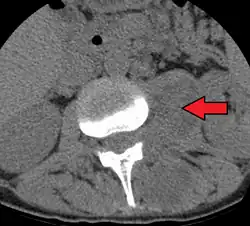

Psoas abscess

Psoas abscess is a collection of pus (abscess) in the iliopsoas muscle compartment.[1][2][3] It can be classified into primary psoas abscess (caused by hematogenous or lymphatic spread of a pathogen) and secondary psoas abscess (resulting from contiguous spread from an adjacent infectious focus).[3]